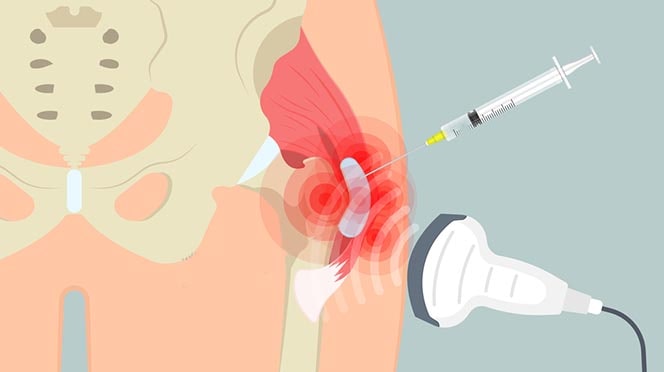

A precisão do guia por ultrassom no procedimento

A infiltração de quadril deve ser realizada com máxima precisão. Para isso, o procedimento pode ser guiado por ultrassom.

Primeiramente, o ultrassom é utilizado para posicionar corretamente a agulha no ponto exato da lesão. O ácido hialurônico, que possui textura espessa e viscosa, é então injetado na articulação. O procedimento é rápido e geralmente bem tolerado.

Nas primeiras 48 horas, a dor pode não melhorar imediatamente. Após esse período, é comum o paciente relatar alívio progressivo e melhora da mobilidade.

O risco de complicações é baixo, por se tratar de técnica pouco invasiva. Pode ocorrer discreto inchaço ou dor local temporária. Por isso, a experiência do especialista é fundamental para garantir segurança, conforto e eficácia.